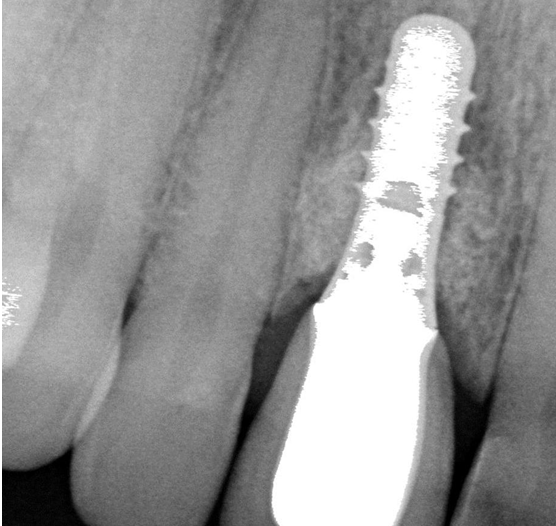

Ασθενής ετών 57 προσήλθε στο ιατρείο παραπονούμενος για ήπιο πόνο, φλεγμονή και πυορροή στο εμφύτευμα που είχε τοποθετηθεί προ τριετίας. Κλινικά και ακτινογραφικά διαπιστώθηκε οστική απώλεια γύρω από το εμφύτευμα (οστική βλάβη- κρατήρας). Ακολούθησε χειρουργική διάνοιξη στην περιοχή, καθαρισμός του εμφυτεύματος, τοποθέτηση οστικού μοσχεύματος και μεμβράνης (οστική ανάπλαση).

Έξι μήνες μετά κλινικά η βλάβη έχει επαλειφθεί και ακτινογραφικά εμφανίζεται οστική πλήρωση αυτής.

Περιεμφυτευματική βλάβη - Αρχική Ακτινογραφία

Περιεμφυτευματική βλάβη - Τελική Ακτινογραφία